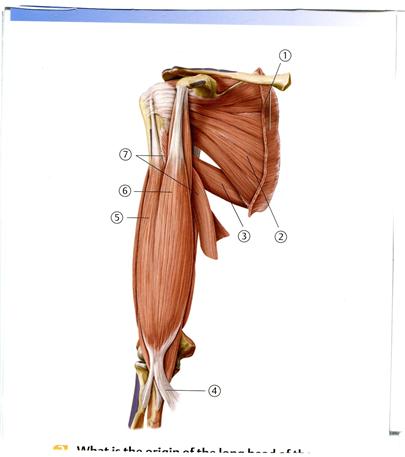

++Е Көлденең өсінді

41. Төменде көрсетілген суреттегі белгіленген № 6 бұлшықетті атаңыз.

А. Айдаршықаралық шұңқырша

D. Медиальді айдаршық буын беті

49. Төменде көрсетілген суреттегі белгіленген № 3 бұлшықетті атаңыз.

А. Алдыңғы тісшеленген

В. Екібасты бұлшықеттің ұзын басы

С. Екібасты бұлшықеттің қысқа басы

++D. Жауырынасты

Е. Үлкен жұмыр